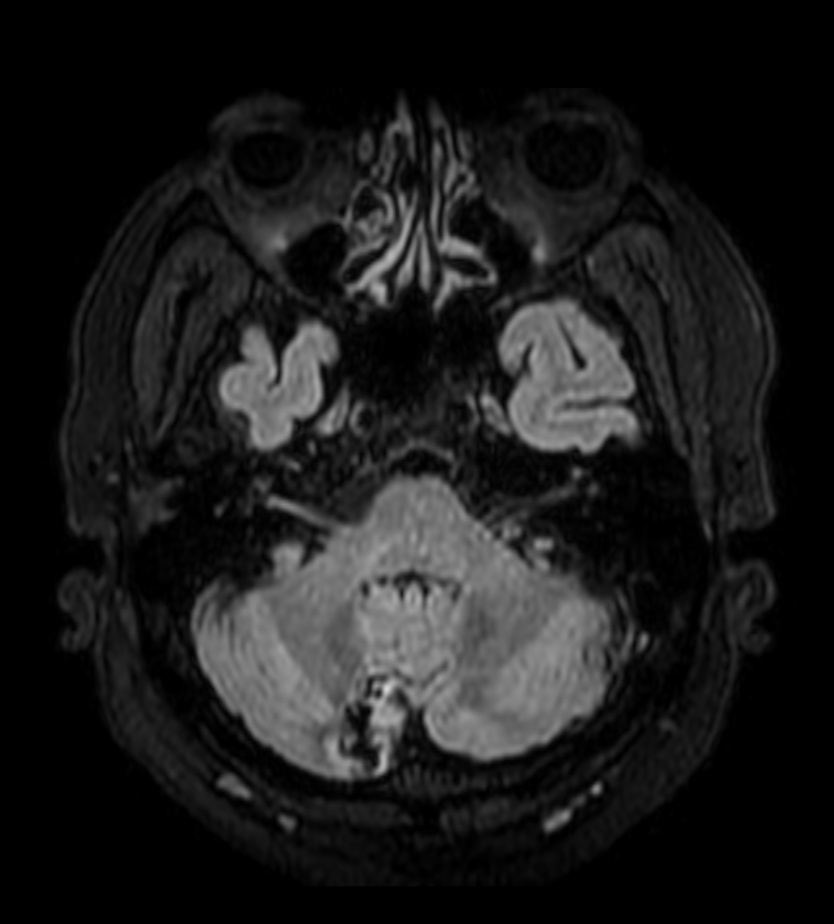

Patient with a lesion in the cerebellum. The ExamCard includes Compressed SENSE to accelerate the entire exam and techniques for motion reduced imaging (MultiVane XD), 3D imaging to acquire high resolution data in multiple directions, 3D susceptibility weighted imaging (SWIp), angiography sequences (Time-of-Flight and Contrast-Enhanced MRA with both arterial and venous phases), DTI with MultiBand SENSE to acquire a high number of diffusion directions in a short scan time and EPIC Brain to bring down any residual distortion.

SWIp (minIP)